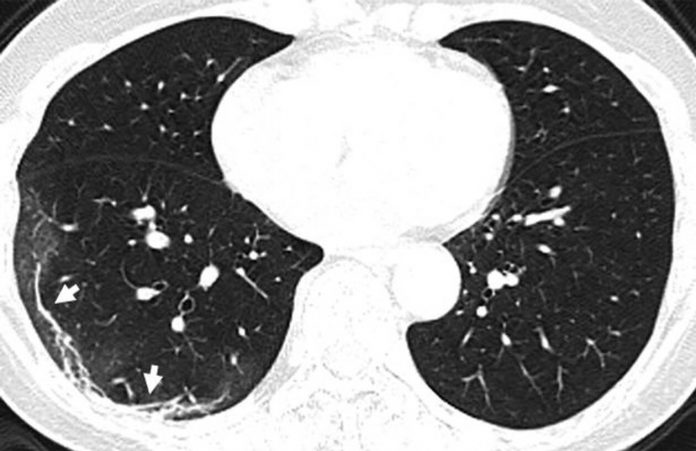

Στην δημοσιότητα δόθηκαν από την Ραδιολογική Κοινότητα της Βορείου Αμερικής, ακτινογραφία πνευμόνων ασθενών, οι οποίοι είχαν προσβληθεί από τον κοροναϊό, οι οποίες προκαλούν ανατριχίλα.

Να σημειώσουμε πως οι ακτινογραφίες αυτές που δόθηκαν στην δημοσιότητα είναι από ασθενείς από την Κίνα που νόσησαν με επιπλοκές, οπότε δεν έχουν καμία σχέση με το αν νοσήσει κάποιος ο οποίος δεν αντιμετωπίζει προβλήματα υγείας.

Οι πνεύμονες μιας 59χρονης με υψηλό πυρετό.